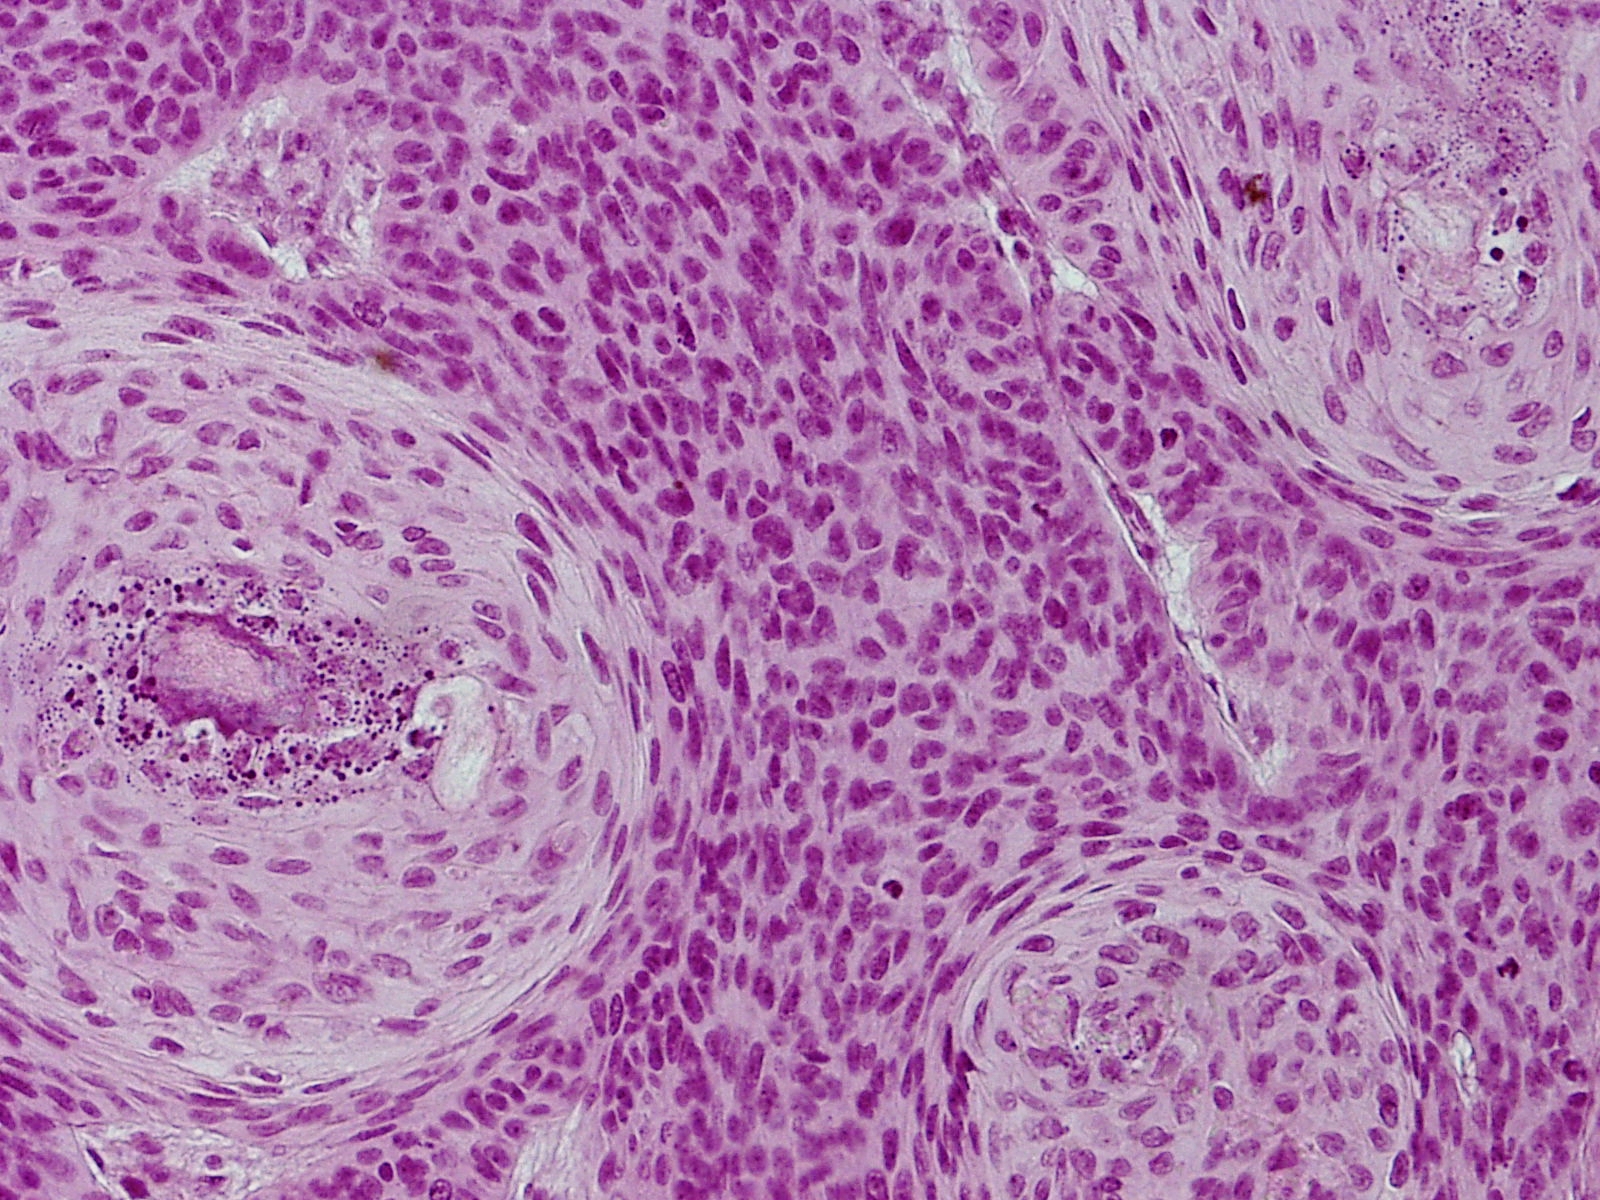

PA nodulair basaalcelcarcinoom:

Verbonden met de epidermis of de haarfollikels, soms schijnbaar zelfstandig

zonder duidelijke relatie hiermee, ziet men epitheel eilanden gekenmerkt door

donkere cellen met relatief weinig cytoplasma. De celgrenzen zijn soms niet

duidelijk en het geheel lijkt te bestaan uit een massa van donkere celkernen,

elk met een smal licht protoplasmarandje en omgeven door een rand van kernen

van hetzelfde type die als palissaden naast elkaar staan op dezelfde wijze als

in het stratum basale en rond de haarpapil. Er zijn geen celbrugjes te zien

zoals in het stratum spinosum; de door de palissadelaag ingesloten kernen lijken

wat ongeordend bij elkaar te liggen. De kernen hebben een regelmatig, uniform

aspect, ze bezitten geen anaplastische kenmerken en tonen geen abnormale mitosen.

Meestal zijn er hoorncysten in het epitheel; er is een directe overgang van

'basaloide' cellen in hoorn en niet, zoals in de epidermis, via voorstadia zoals

stratum spinosum of stratum granulosum. Deze hoorncysten komen voor bij vrijwel

alle vormen en varianten van het carcinoma basocellulare, soms echter vormen

ze een hoofdkenmerk. Het bindweefsel in de cutis blijkt in relatie tot de tumorcellen

mee te groeien, er is geen infiltratieve groei. Dit blijkt o.a. uit het feit

dat zich bij de fixatie vaak spleten vormen op de grens van carcinoom-bindweefsel,

een verschijnsel dat niet bij carcinoma spinocellulare (waarbij wel infiltrerende

groei plaatsvindt) te zien is. Het bindweefsel rond de tumorveldjes bevat vele

jonge fibroblasten en is hier bovendien metachromatisch (zure mucopolysacchariden)

en PAS-positief als bij de haarpapillen. De vaten zijn toegenomen en verwijd;

er is soms opvallend weinig cellulair infiltraat. Soms echter bevindt zich,

vooral vlak bij de tumorveldjes, enig lymfocytair infiltraat. Is ulceratie opgetreden

dan neemt het infiltraat toe en bevat het aan de oppervlakte soms talrijke polynucleaire

granulocyten. Carcinoma basocellulare komt niet aan de slijmvliezen voor. Zie